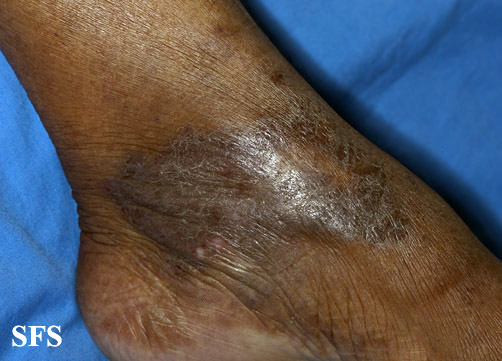

acroangiodermatitis